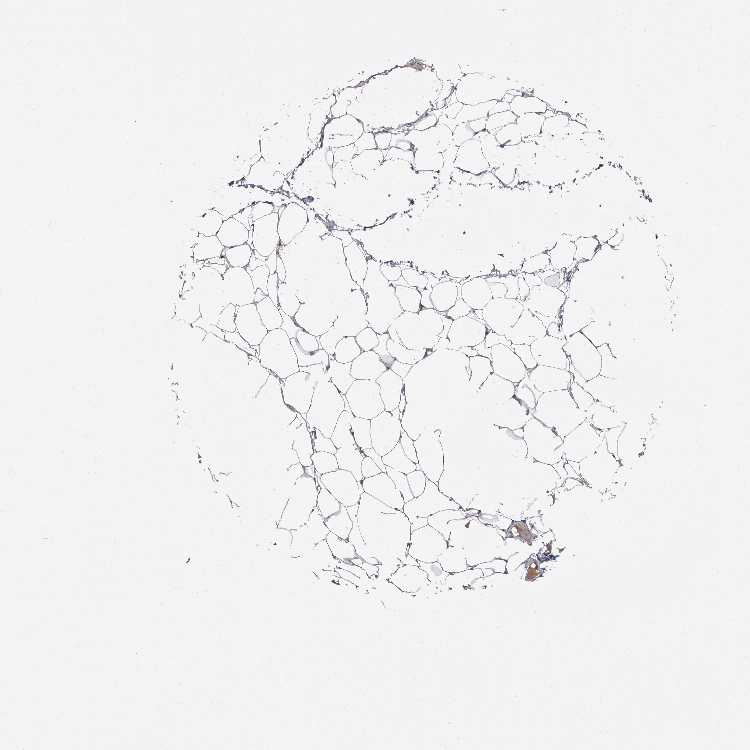

SOFT TISSUE 1 - Antibody stainingi

Antibody staining in the annotated cell types in the current human tissue is reported as not detected, low, medium, or high, based on conventional immunohistochemistry profiling in selected tissues. This score is based on the combination of the staining intensity and fraction of stained cells.

Each image is clickable and will lead to virtual microscopy that enables deeper exploration of all samples and also displays staining intensity scores, fraction scores and subcellular localization as well as patient and tissue information for each sample.

Antibody HPA009128Antibody HPA029564

Chondrocytes Medium-

Fibroblasts LowNot detected

Peripheral nerve Not detectedNot detected

SOFT TISSUE 2 - Antibody stainingi

Chondrocytes -Not detected

Fibroblasts MediumNot detected

Peripheral nerve Low-